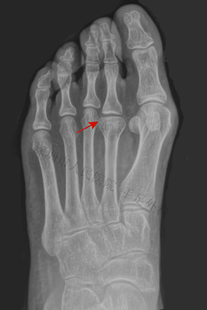

图6:患者拇外翻畸形,籽骨部位行走时疼痛(箭头),可见痛性胼胝(老茧)

图7:X光片示第二跖骨头无菌性坏死(Freiberg病),跖骨头塌陷,跖骨短缩。上述病变导致拇趾籽骨局部应力增加,导致内侧籽骨增生,最终形成籽骨炎

图8:籽骨轴位片示内侧籽骨增生,右图为局部放大图(箭头)